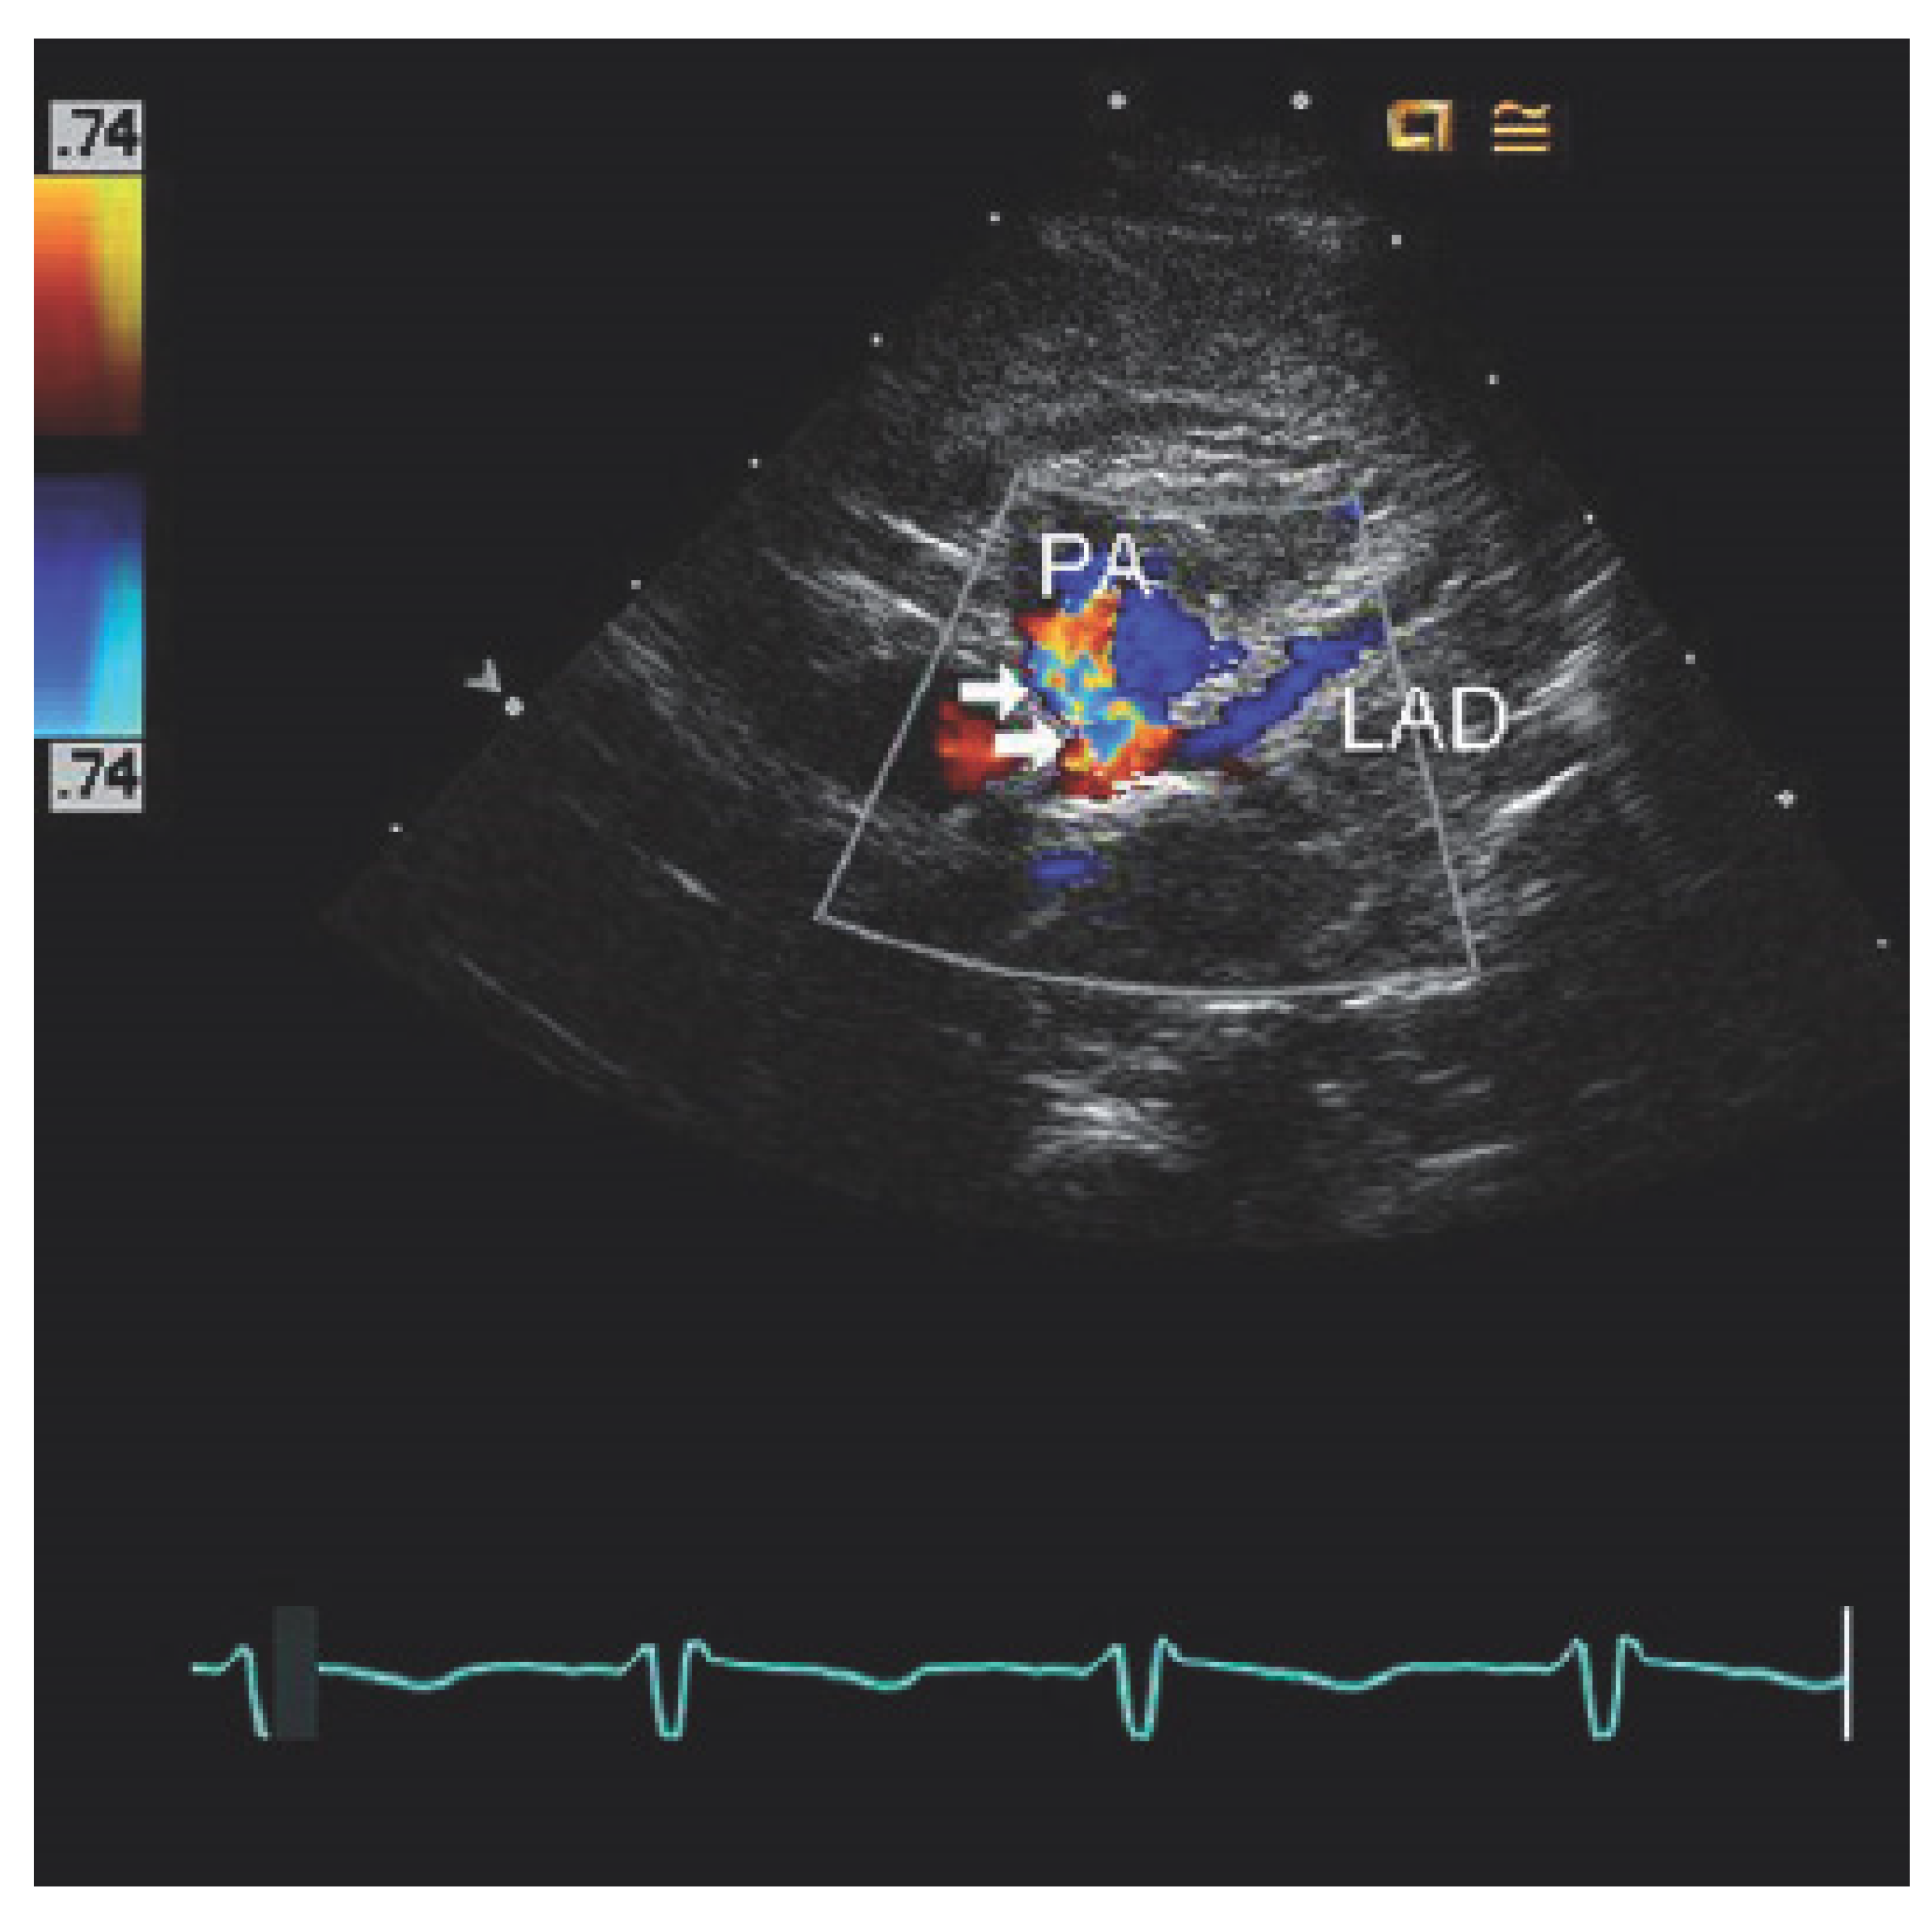

Invasive coronary angiography (ICA) was the standard for ALCAPA diagnosis as it depicted the course of the anomalous coronary artery; however, it has been largely replaced by noninvasive diagnostic testing. However, during the course of a workup for angina, the patient may undergo ICA and be found to have ALCAPA incidentally. Typical findings on ICA include a dilated and tortuous right coronary artery with multiple collaterals to the left coronary system; anomalous flow into the pulmonary artery can also be seen (Figure 1) [7]. Transthoracic echocardiogram (TTE) with color Doppler is a safe, readily available, inexpensive, and portable noninvasive method for initial investigation used in all patients (Table 1). Echocardiographic findings indicative of ALCAPA include visualization of the left coronary artery originating from the pulmonary artery (Figure 2), retrograde flow from the left coronary artery to the pulmonary artery (Figure 3), dilated and tortuous right coronary artery, lack of the left coronary artery at aortic origin, significant and dilated collateral coronary arteries, mitral regurgitation, left ventricular dysfunction with regional wall motion abnormalities, and enhanced echogenicity of papillary muscles [9,10,11]. The parasternal short-axis acoustic window on TTE provides the best views of the origins of the coronary arteries. Increased flow in the minor coronary arteries due to the collateral flow from the right to the left coronary artery may be detected by lowering the Nyquist limit. In younger patients with dilated right coronary artery, collateral arterial flow in the ventricular septum may be seen and misdiagnosed as multiple trabecular ventricular septal defects. In order to distinguish between these two, pulse-wave Doppler should be performed: continuous flow in the collateral vessels is noted in patients with ALCAPA, while systolic flow into the right ventricle is noted in patients with ventricular septal defects [11]. Transthoracic echocardiogram, while fast and easy, has poor spatial resolution, making it difficult to identify and visualize the arteries; thus, it should be supplemented with further diagnostic testing such as computed tomography angiography (CTA), magnetic resonance angiography (MRA), or ICA [4].

Figure 3. Echocardiography of anomalous left coronary artery from the pulmonary artery show-ing retrograde flow in the left anterior descending (LAD) coronary artery. Flow in the LAD is blue as it moves away from the transducer toward the pulmonary artery (PA), which is abnormal be-cause it should flow away from the aortic root (red Doppler signal) rather than toward it. A turbu-lent flow signal (arrows) is also seen in the pulmonary artery as the anomalous left coronary ar-tery empties into the low-pressure pulmonary artery. Used with permission from Eidem, Benjamin W., Jonathan Johnson, Leo Lopez and Frank Cetta. Echocardiography in Pediatric and Adult Congenital Heart Disease. Available from: Wolters Kluwer, (3rd Edition), 2021: 514-530. [13].